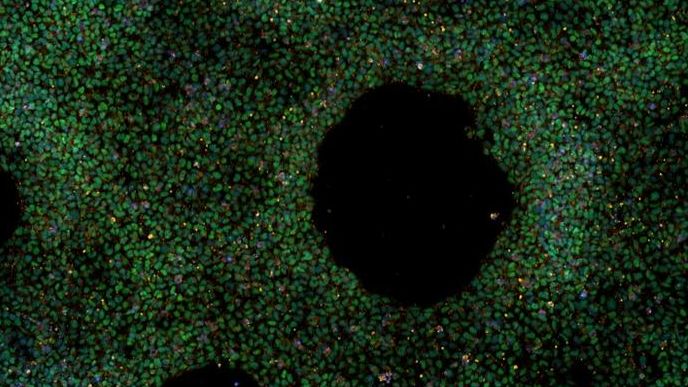

Per facilitare la ricerca in questa direzione, i ricercatori del nuovo studio hanno messo a punto una banca di cellule staminali provenienti da oltre 100 individui selezionati in base al Prs. In particolare, circa due terzi dei donatori hanno ricevuto una diagnosi di Alzheimer con un Prs relativamente alto, mentre i restanti erano individui cognitivamente sani, della stessa età e con un Prs basso. Da qui, i ricercatori hanno prelevato le loro cellule del sangue, che sono poi state geneticamente modificate per trasformarle in cellule staminali pluripotenti indotte (Ipsc), ossia cellule immature in grado di generare tutti i tipi cellulari del nostro organismo. Con questo nuovo strumento, quindi, gli scienziati sperano di implementare gli studi sull’impatto delle varianti di rischio nei modelli cellulari di malattia di Alzheimer basati su staminali pluripotenti indotte in laboratorio e, in futuro, di arrivare a nuove potenziali strategie di trattamento e prevenzione della patologia.